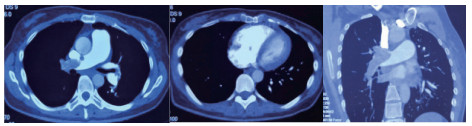

1 经典的挽救性溶栓治疗策略可能带给医生更多的是被动和难度例1 男性,28岁,体质量90 kg。主诉“胸闷、憋气1周加重1 d”。既往:体健;喜久坐(平均10~15 h/d);否认手术史、外伤史;入院查体:神志清楚,体温36.8℃,血压128/80 mmHg(1 mmHg=0.133 kPa),脉搏120次/min,呼吸26次/min,脉氧饱和度96%(安静,空气氧),未见明显乏氧征。双肺呼吸音清,未闻及干湿性啰音。心率120次/min,心律齐,P2 > A2,心界无扩大,无杂音。腹软,无压痛,肠鸣音正常,双下肢无浮肿。神经系统查体未见异常。血气分析(空气氧)提示pH 7.514,PaCO2 27.2 mmHg,PaO2 67.1 mmHg,SaO2 95.0%;D-Dimer:3 035 ng/mL,FDP 33.08 μg/mL,FBG 4.520 g/L;PLT 179.0 G/L,TNI 0.08 ng/mL,BNP 882.00 pg/mL;ALT 38 U/L,AST 17 U/L,CREA 82.6 μmol/L,血Na+、K+、Cl-正常范围;超声心动图(Ultrasonic Cardiogram,UCG)提示:右心增大,肺动脉主干及右肺动脉增宽,肺动脉主干32 mm,三尖瓣反流(重度),反流面积8.6 cm2,TI法估计SPAP为67 mmHg、左室舒末内径50 mm、左室E/A:45/38 cm/s, 左室壁厚度及运动正常,未见节段性室壁运动障碍;双下肢静脉超声提示左侧股静脉血栓形成可能(完全型)。心电图(图 1所示)提示窦性心动过速;肺动脉增强CT(Computed tomographic pulmonary angiography, CTPA)提示双肺主干明确充盈缺损(图 2所示)。入院诊断:急性肺血栓栓塞症(中高危)。入院后给予抗凝治疗(依诺肝素钠90 mg,皮下注射,1次/12 h)重叠华法令治疗的第4天D-Dimer升至47 482 ng/mL,第6天2 411 ng/mL。第7天常规复查双下肢超声未见新增血栓形成,复查UCG(当天INR 2.25)提示右心房漂浮血栓,并随心脏蠕动明显(图 3所示)。在准备胸外科手术取栓的过程中出现血压下降至70/40 mmHg,脉氧饱和度降至45%,立即给予气管插管并系统溶栓治疗(r-tPA 100 mg于2 h输注),溶栓治疗1.5 h患者血压逐渐回升并趋于稳定、溶栓治疗3 h自主呼吸开始恢复,于插管3天后(住院第10天)拔出气管插管,成功撤离呼吸机。溶栓过程中曾经出现消化道、气道出血,血红蛋白下降1.9 g/dL,未予输血治疗。溶栓后复查CTPA提示双肺主干血栓负荷明显减少,远段血液灌注明显增加(图 4所示)。

| 图 4 溶栓后的CTPA肺动脉主干血栓负荷明显减少、远段血液灌注明显增加 |